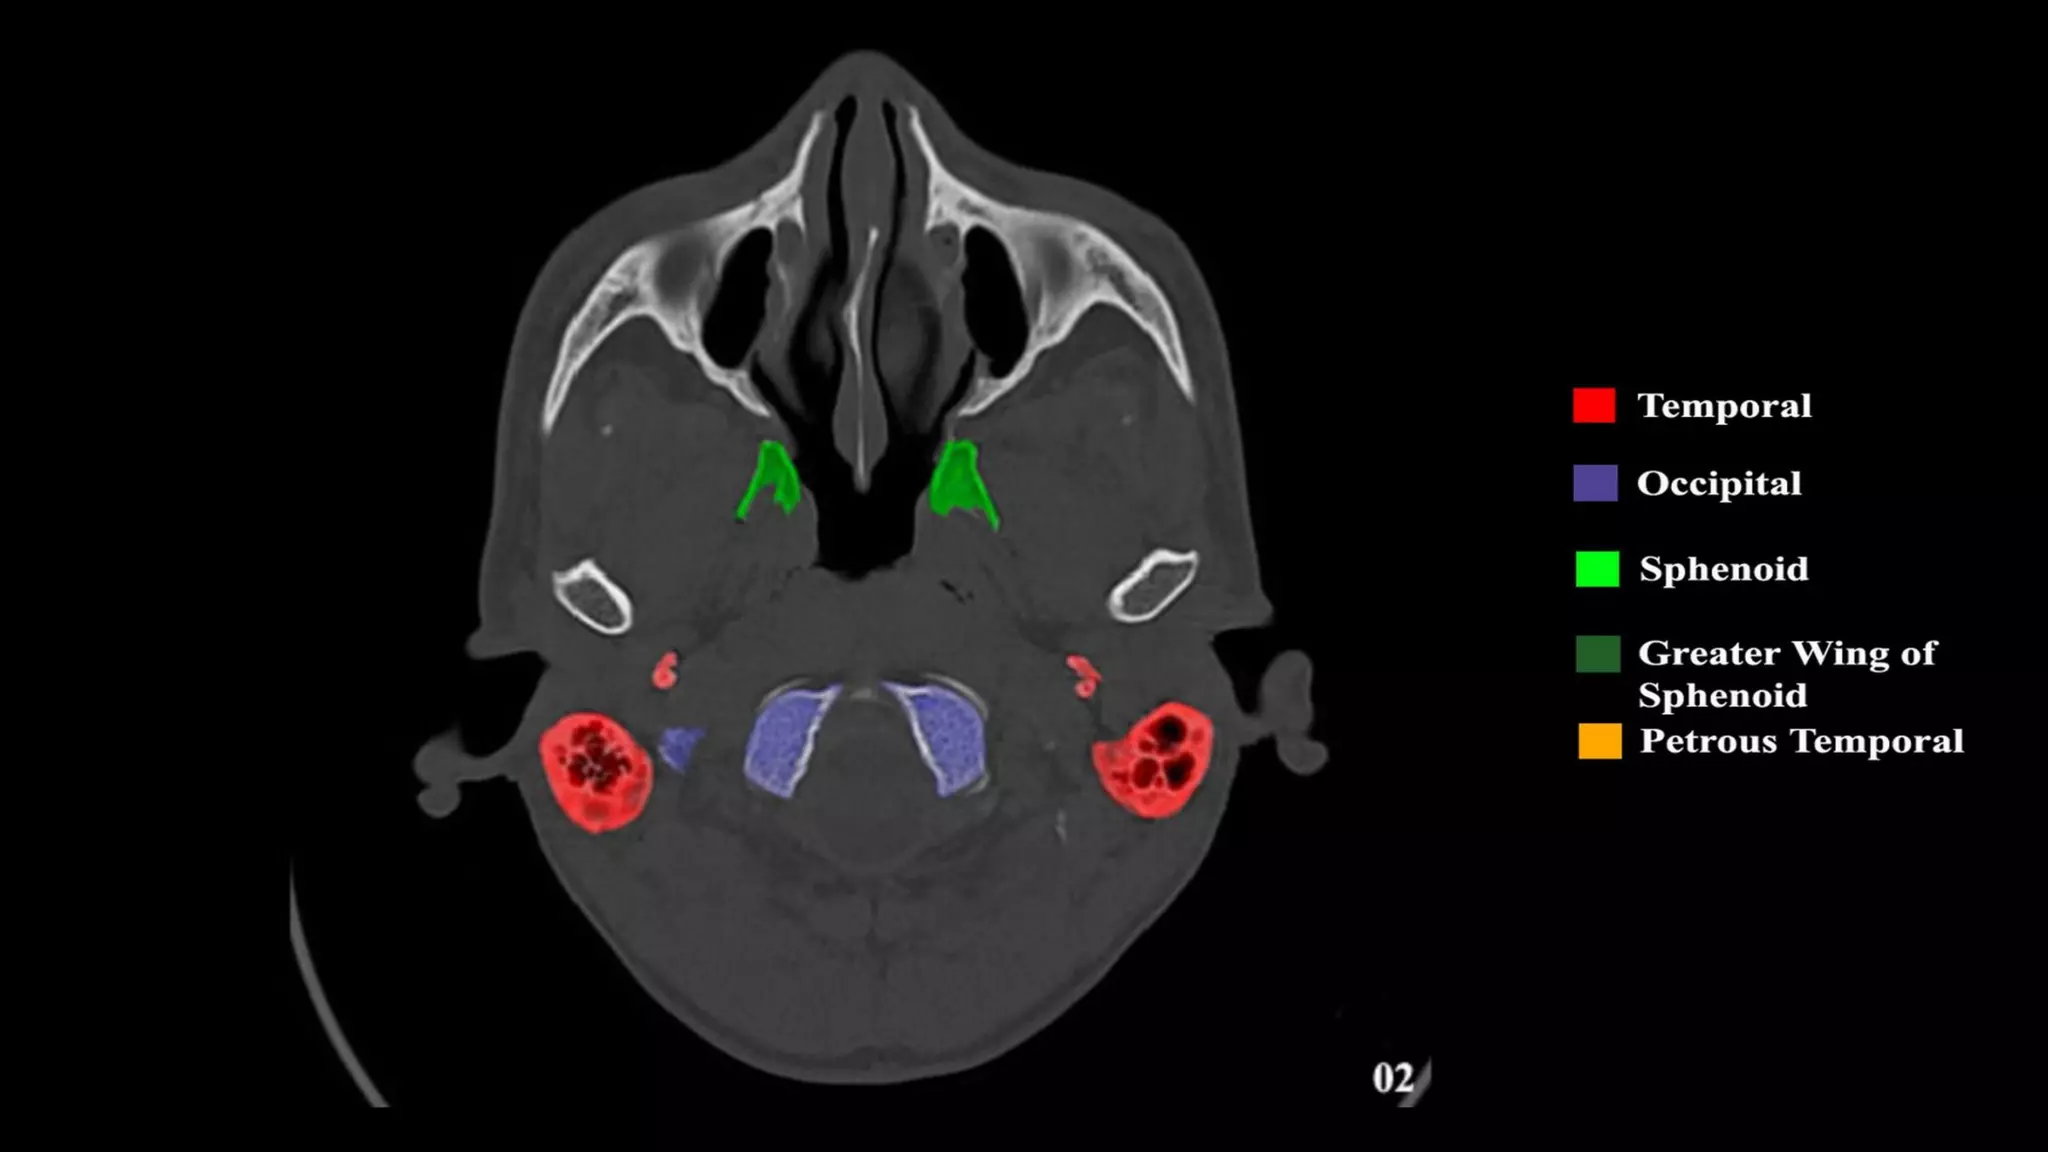

Pseudo-fractures

Extrinsic Fissures &

Sutures